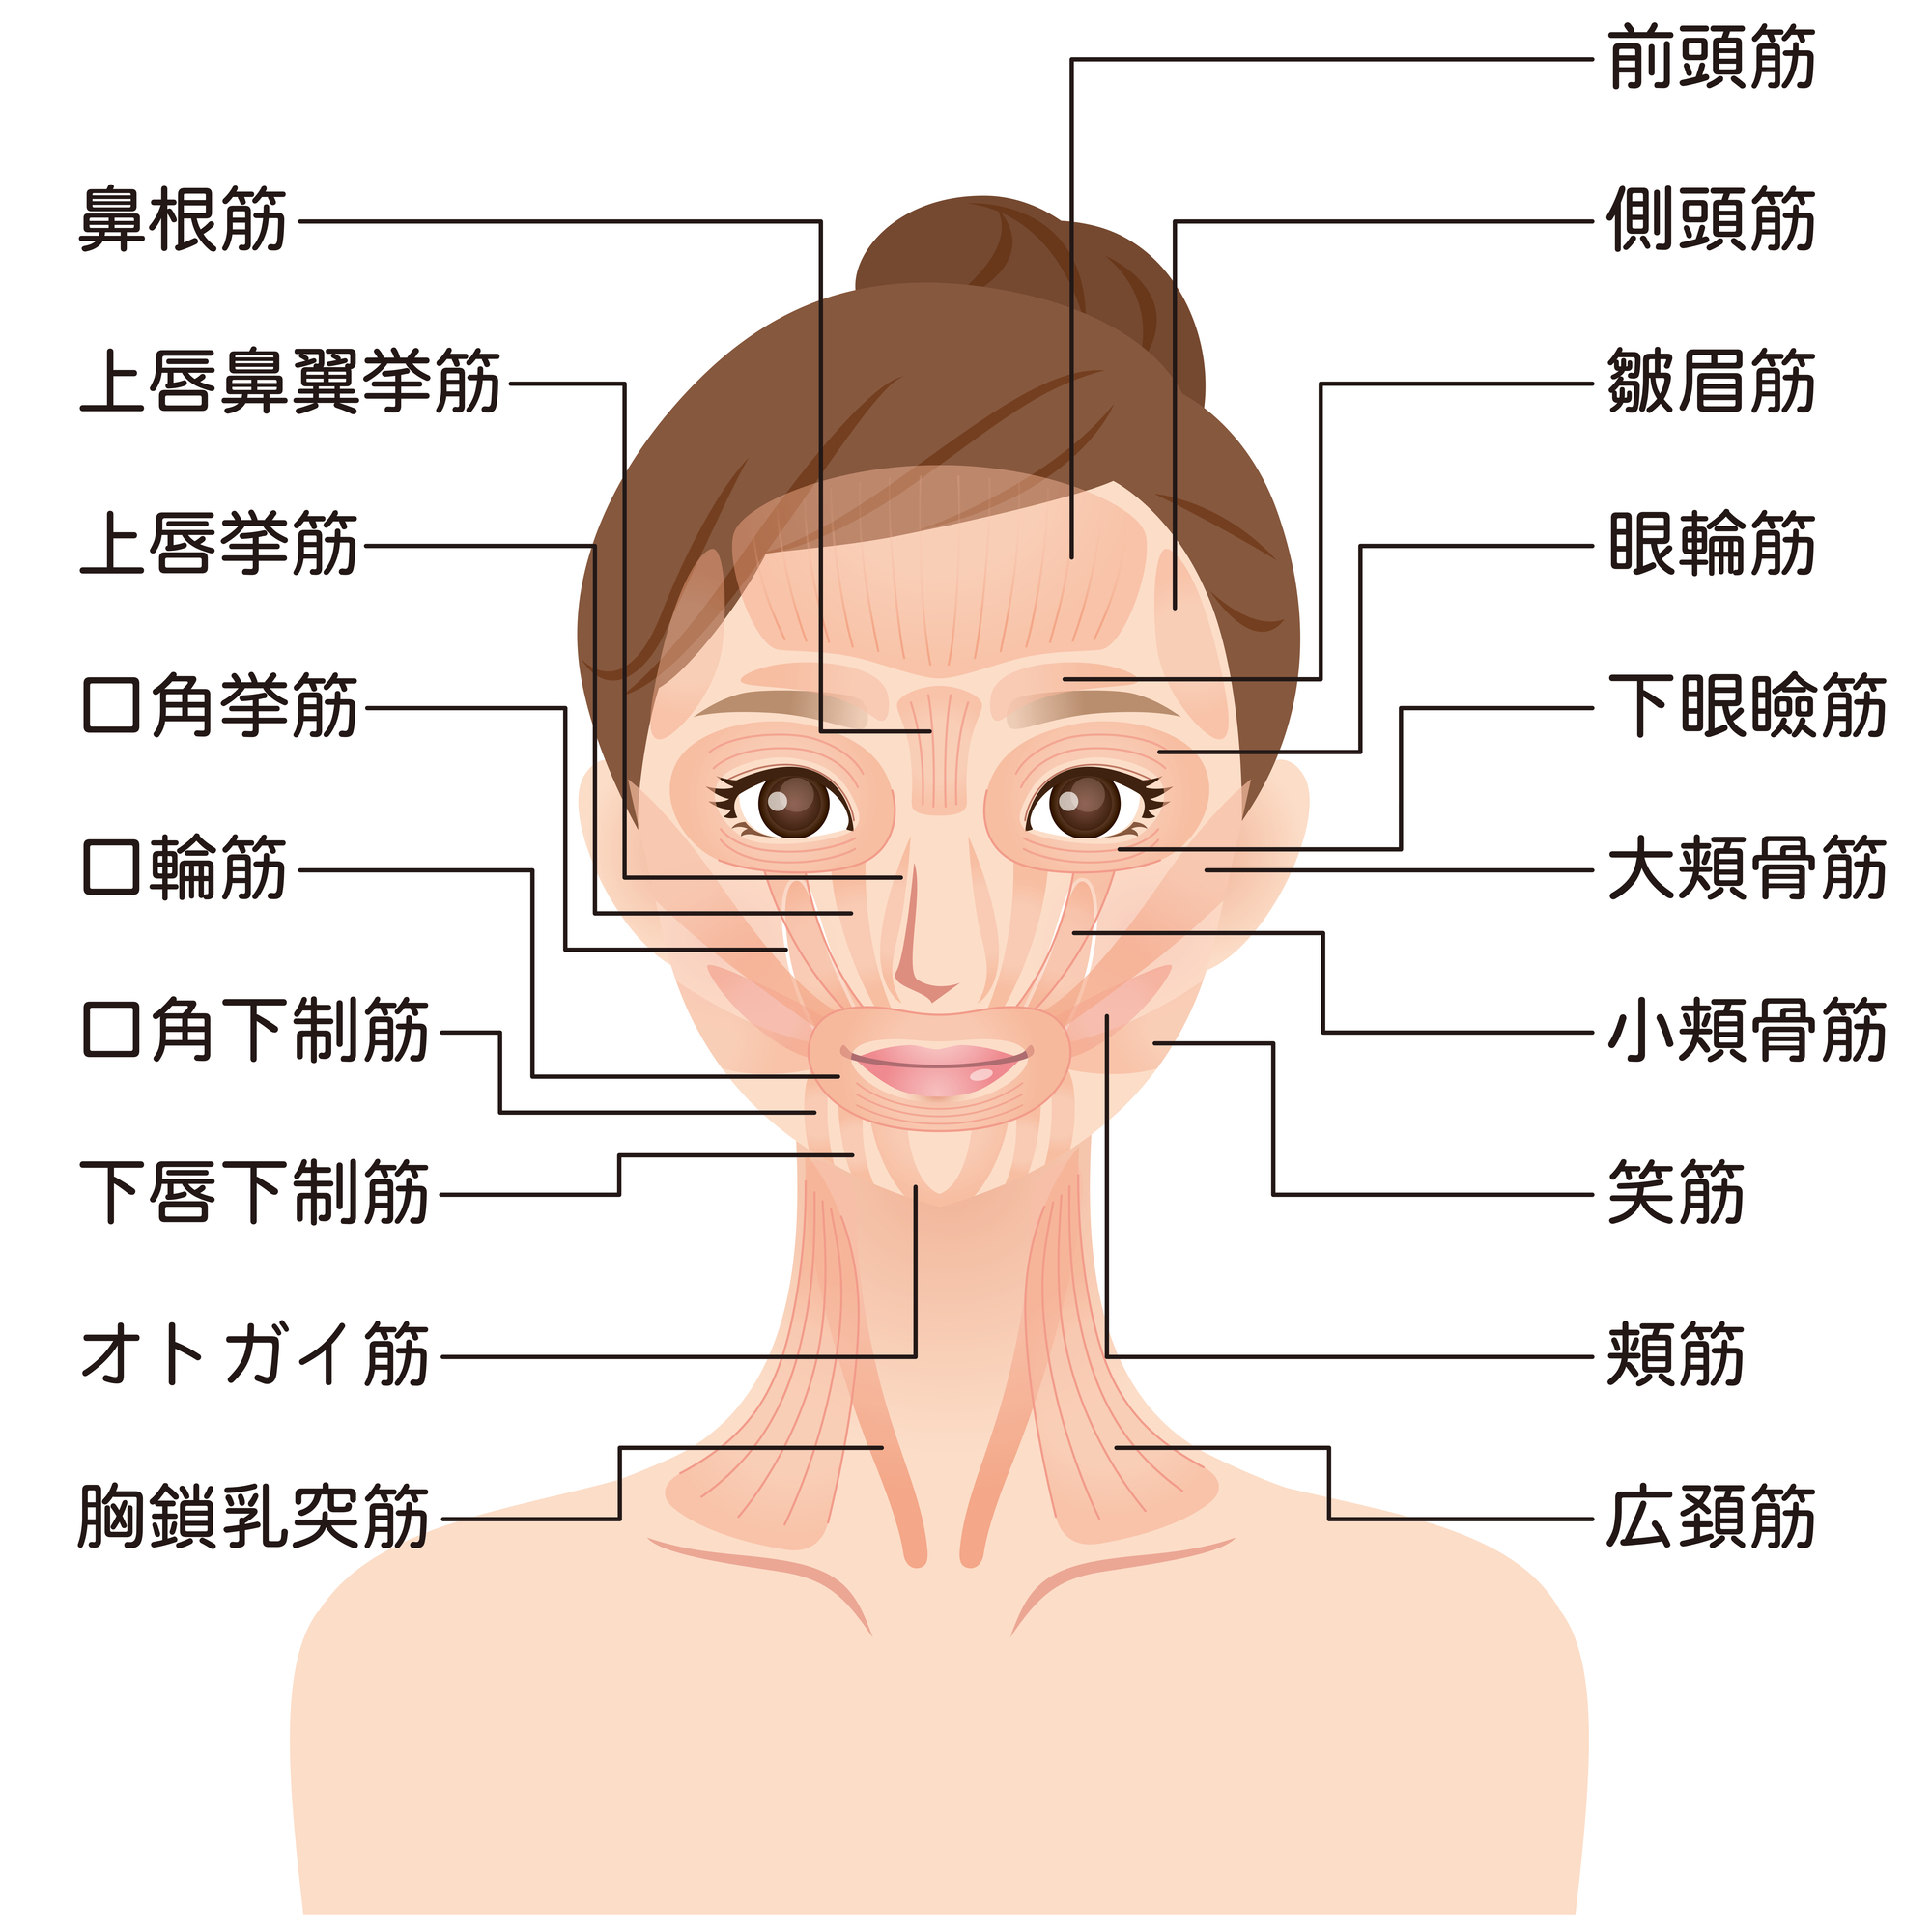

口角が下がるのは歯並びが原因?上げるための生活習慣やトレーニングを紹介